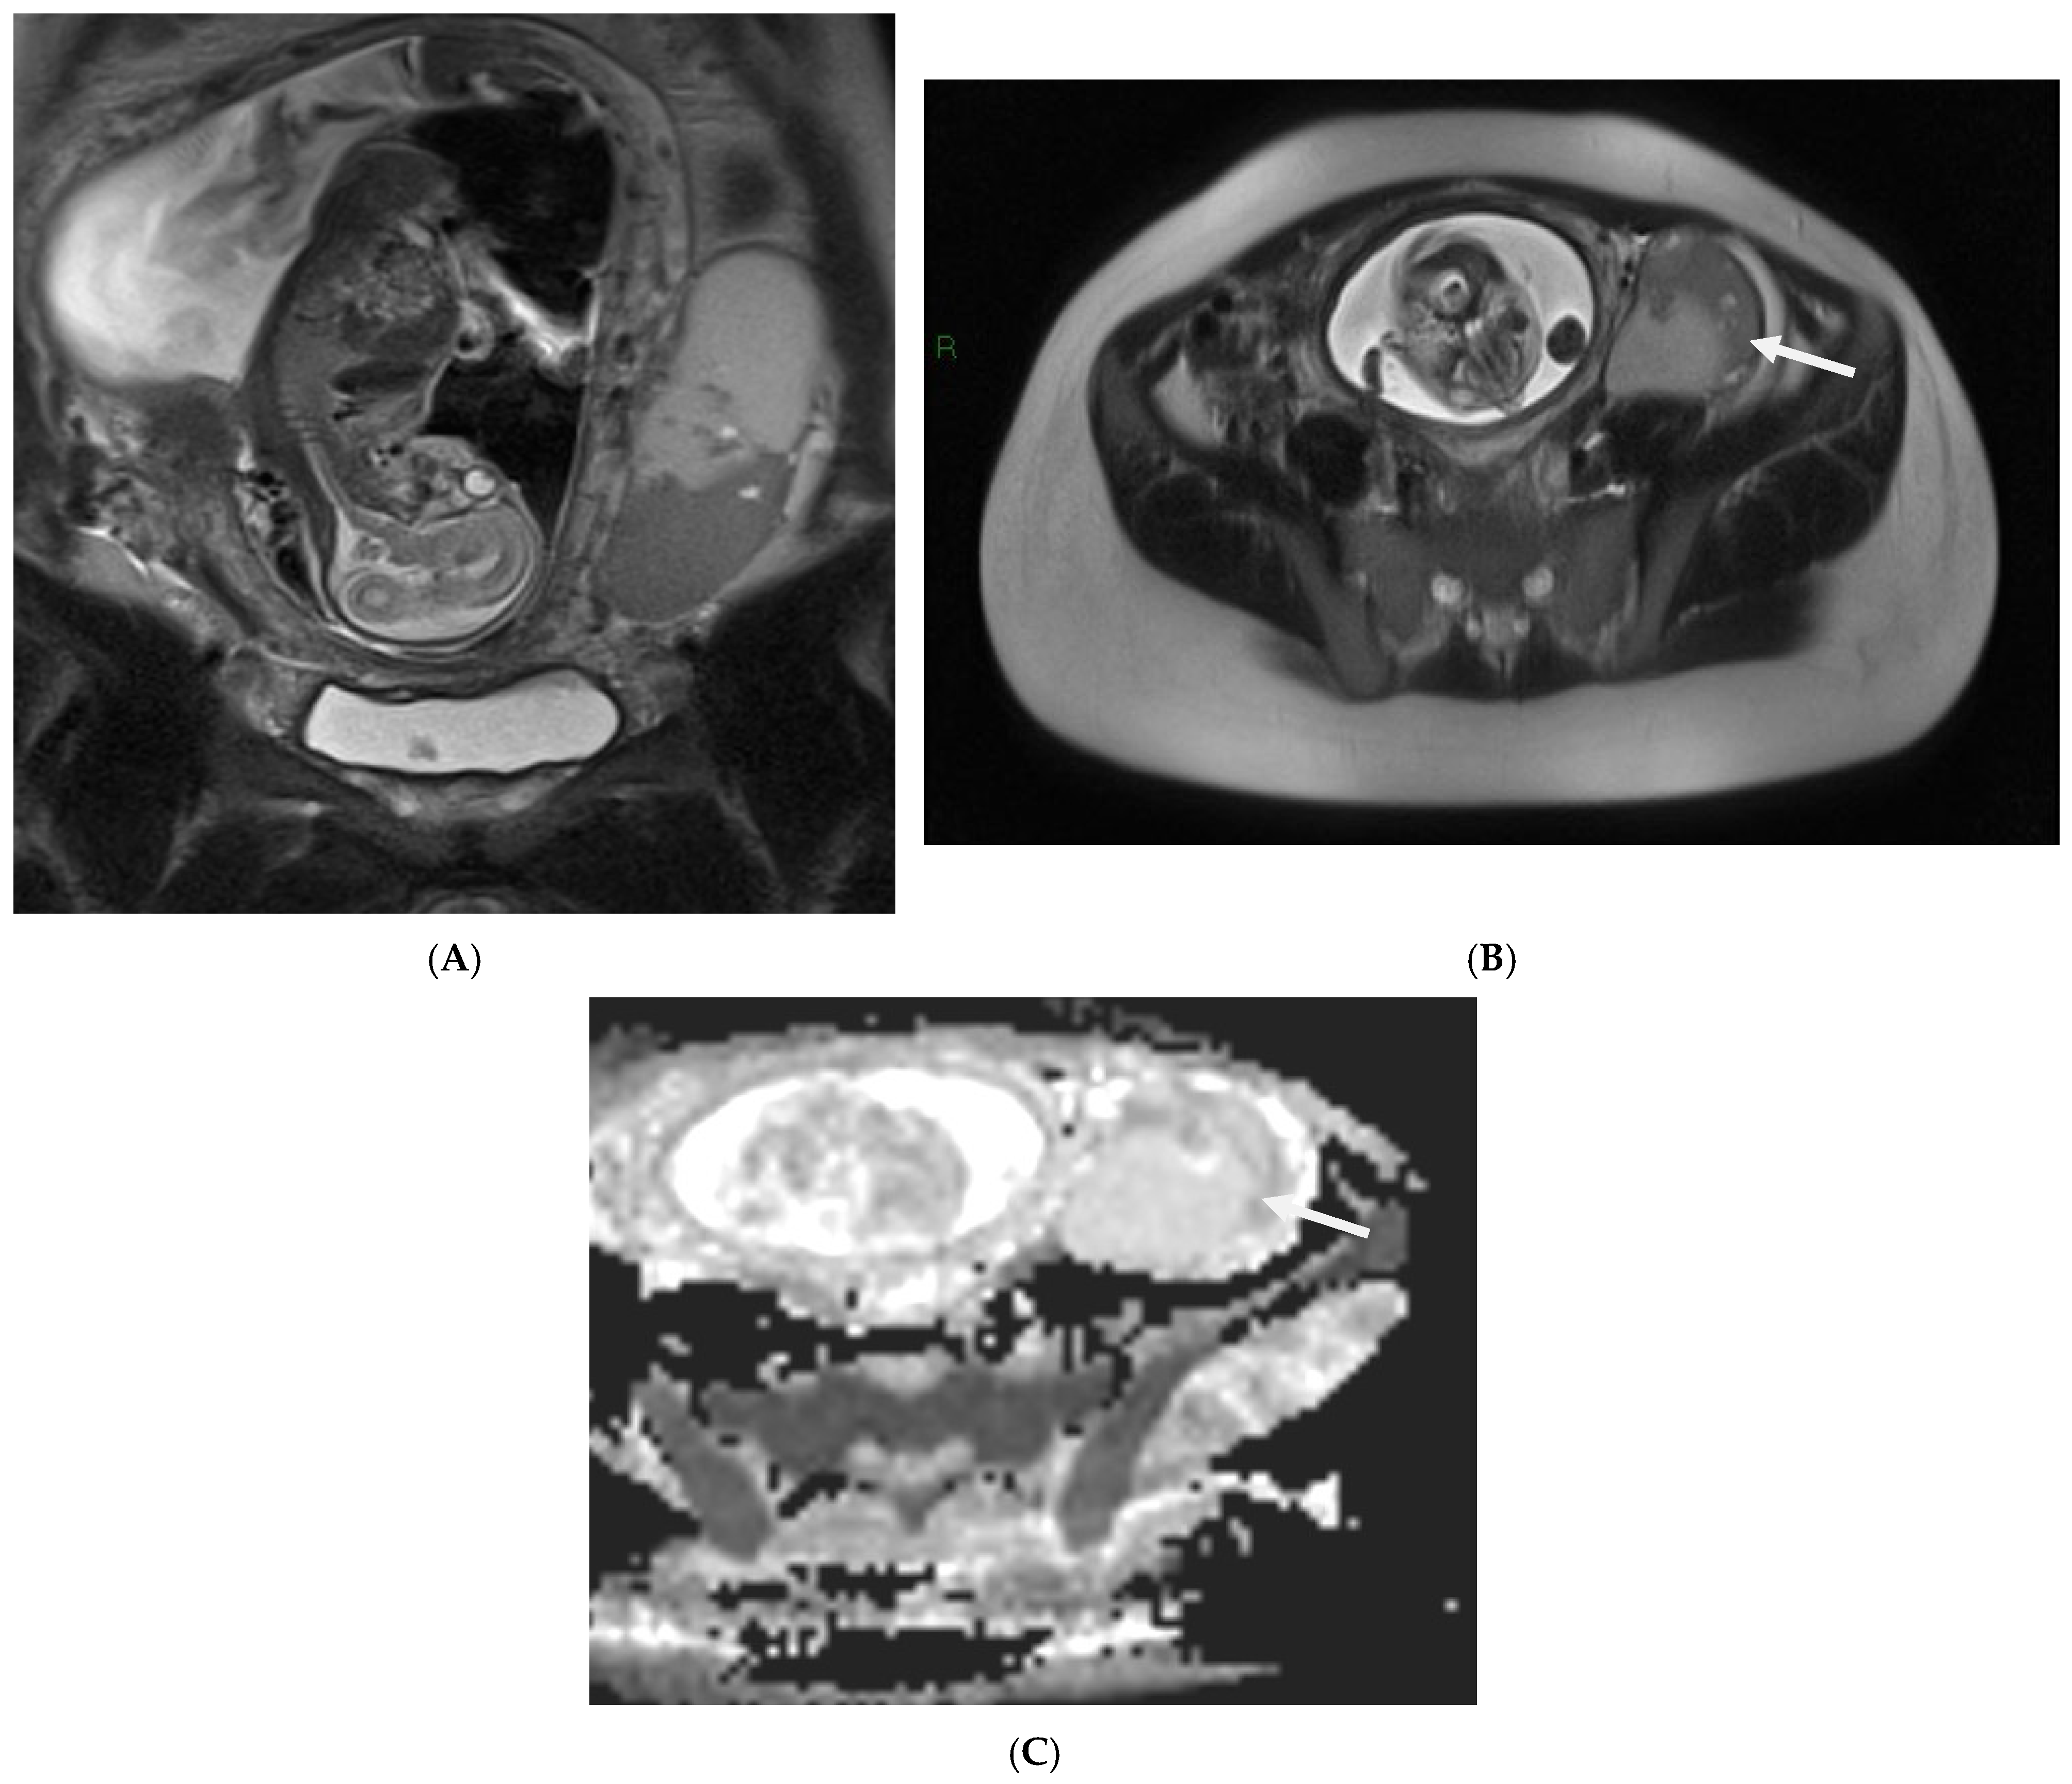

3.5.2. Imaging

- Kawamotoa, S.; Ogawa, F.; Tanaka, J.; Ban, S.; Heshiki, A. Chorioangioma: Antenatal diagnosis with fast MR imaging. Magn. Reson. Imaging 2000, 18, 911–914. [Google Scholar] [CrossRef]

- Masselli, G.; Gualdi, G. MR imaging of the placenta: What a radiologist should know. Abdom. Imaging 2013, 38, 573–587. [Google Scholar] [CrossRef] [PubMed]